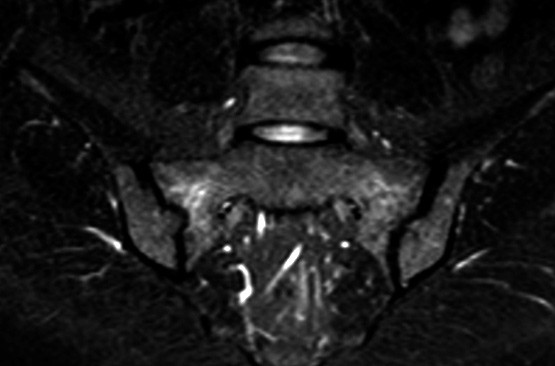

Kvinnen utviklet så gradvis økende smerter fra korsryggen ut i begge glutealregioner. Blodprøver viste normalt kalsium-, lavt fosfat- og forhøyet ALP-nivå, PTH i øvre normalområde, normale 25-OH-vitamin D og 1,25(OH)2-vitamin D-verdier. MR-undersøkelse (STIR-sekvens) viste høysignalforandringer i begge sakralvingene og etter hvert på ileumsiden, tydende på betydelig knokkelødem (bildet til venstre). Det var oppklaringslinjer i sakralvingene som kunne gi mistanke om insuffisiensfraktur bilateralt. Helkroppsscintigrafi viste økt opptak i fremre del av os frontale på begge sider av midtlinjen, i flere costae, begge ileosakralledd og proksimalt i venstre tibia.